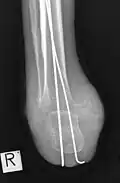

Röntgenaufnahme AP nach tibio-kalkanearer Arthrodese (Pirogoff)

seitl. Aufnahme